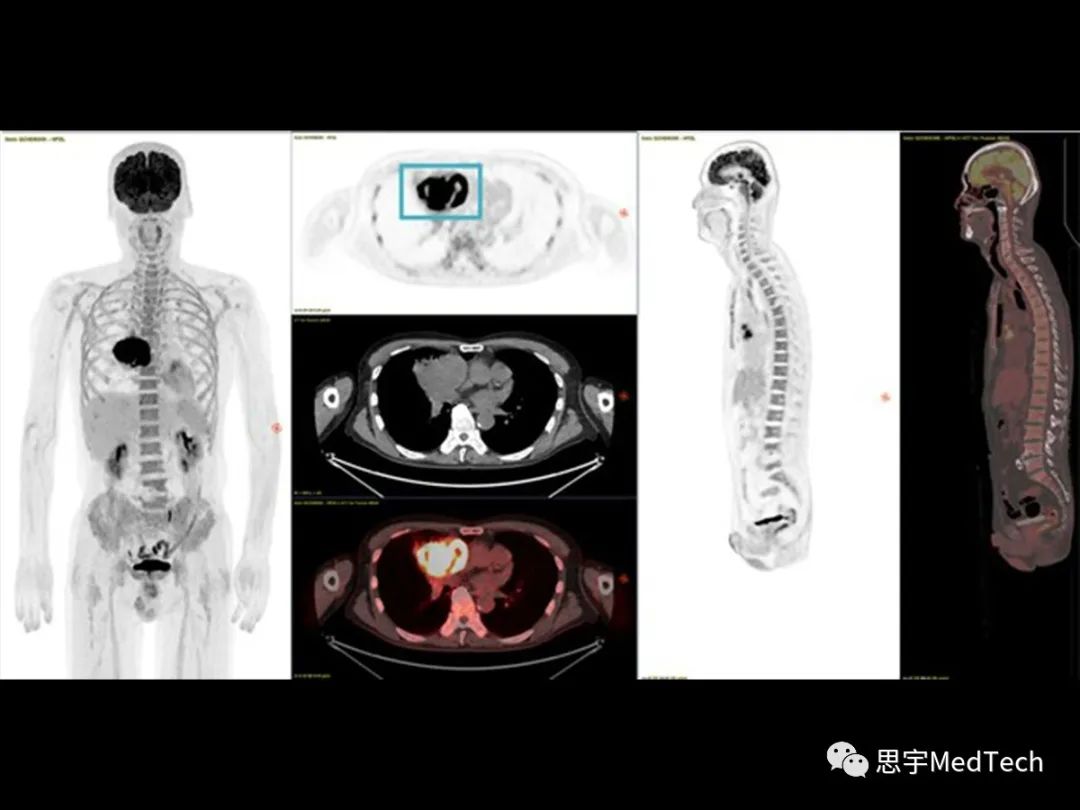

GE医疗生产一系列支持诊疗一体化的工具,例如回旋加速器、PET/CT、PET/MR、SPECT/CT。同时,GE医疗还掌握先进的化学合成技术、成熟的药物诊断业务、先进的癌症治疗方法以及数字化的手段,几乎能够覆盖患者医疗的方方面面,因此能够帮助BAMF Health运营诊疗一体化项目。而BAMF Health则能够为各种类型的癌症提供分子成像,重点关注诊疗一体化,能利用专业知识和美国各地的卫生系统合作,扩大分子成像和诊疗一体化的规模,把这种新疗法的价格压下来,让患者用得起,让临床医生能用上。 GE医疗美国和加拿大部分的总裁兼首席执行官Catherine Estrampes表示:“GE医疗能为诊疗一体化带来重要团队、数据以及决策,为患者提供精准医疗和个性化护理。我们很高兴能与BAMF Health展开专业合作,共同推进诊疗一体化的使用和整合。” ▲Anthony ChangBAMF Health的创始人兼首席执行官Anthony Chang博士表示:“诊疗一体化的针对性能帮助为罹患疑难癌症的患者提供个性化服务,这种治疗方式在治疗阿尔茨海默病这样的疾病方面也大有可为。我们通过与GE医疗合作,能够在这个快速发展的领域中推动创新。”